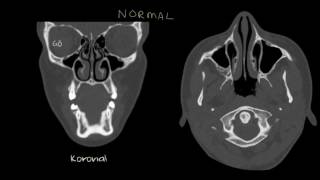

Nazal Polipler (Solunum Sistemi Hastalıkları | Sağlık Bilgisi ve Tıp)

Burun polipleri neden olur? Nasıl belirti verir?

Nazal Polip (Burun Polipleri) Nasıl Tedavi Edilir?

Nazal polip nedenleri nelerdir? Tedavisi nasıldır?